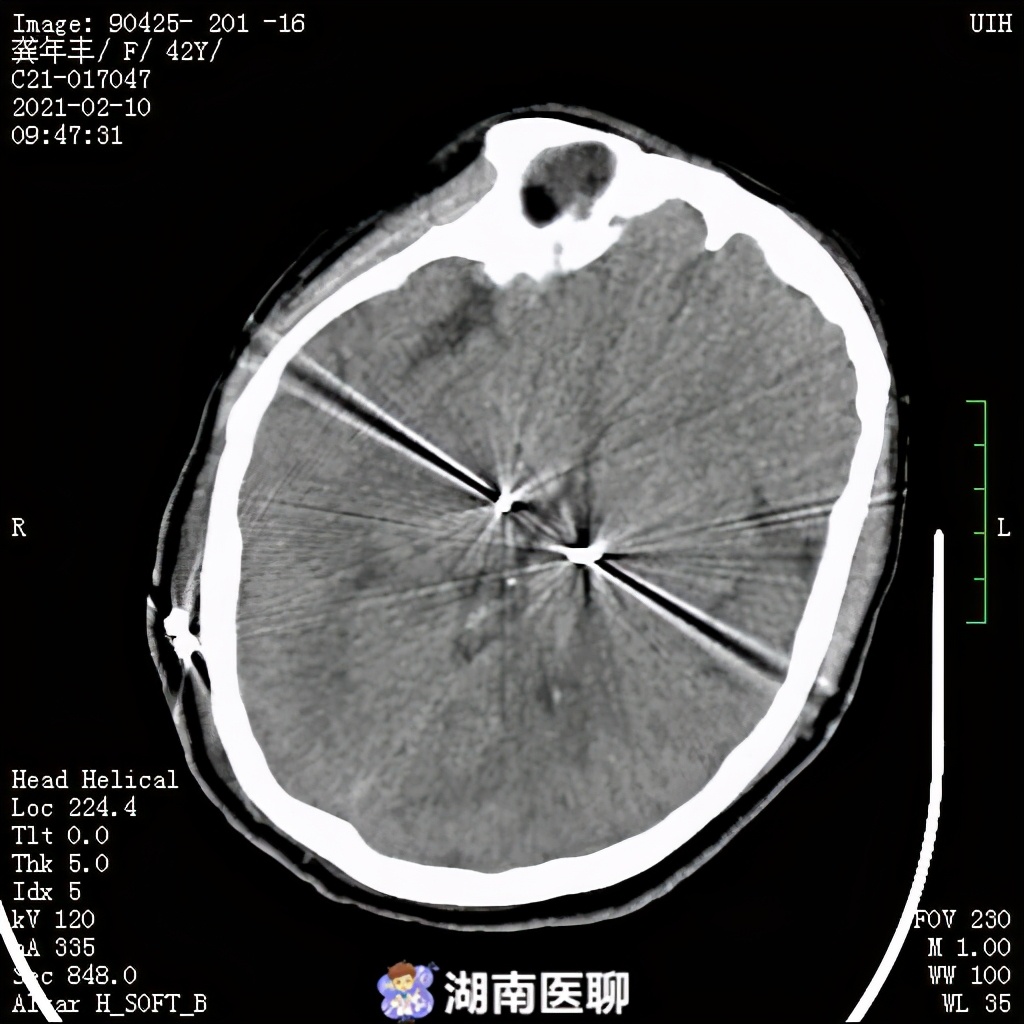

手术过程十分顺利,术后复查头颅CT确定电极置入与计划靶点位置一致,手术获得成功。

术后复查CT显示,“脑起搏器”准确无误植入靶点丘脑底核(STN核)。